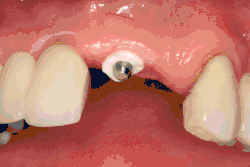

The area of the mouth that is missing a tooth is identified.

An area with a single missing tooth

An incision is made across the area and the flap of gingiva is opened to show the bone of the jaw.

An incision is made across the gingiva, and the flap of tissue is reflected to show the bone of the jaw.